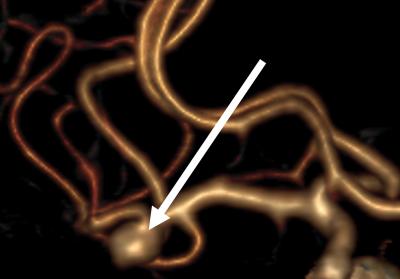

Image Source: The middle cerebral artery bifurcation aneurysm image is credited to Miikka Korja and is adapted from the University of Helsinki press release.